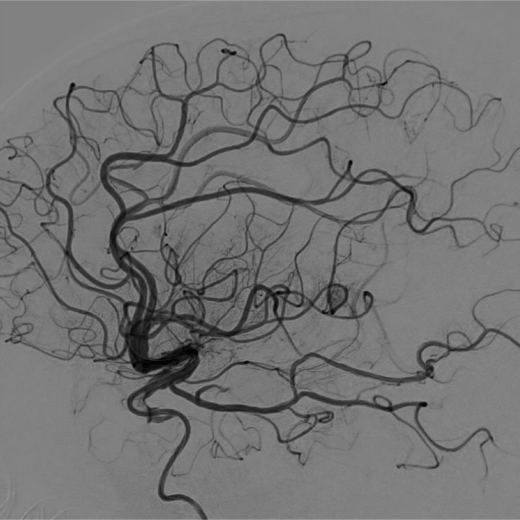

左侧大脑中动脉闭塞支架取栓1例

图片尺寸1355x996

秦进兴,男,78岁.左侧大脑中闭塞,2019第一取

图片尺寸2000x2667

中国神介500人群病例集锦第239期左侧大脑中动脉慢性闭塞再通治疗1例

图片尺寸520x520